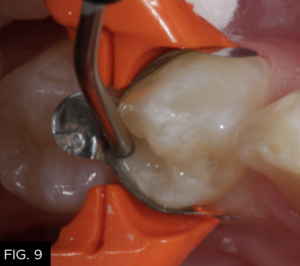

The first layer of composite is placed using a flowable composite (Evanesce Flow, Clinician’s Choice) to a thickness of about .5 millimeters. (FIG. 9) The flowable composite will “flow” into all the irregular areas of the preparation lessening the chance of creating voids between the adhesive and the first layer of composite and once cured, create an oxygen-inhibited layer to bond subsequent layers of composite material. After light-curing for 20 seconds (FIG. 10), the next step is to layer in the conventional type composite material.

The first increment of composite, a flowable resin (Evanesce Flow, Clinician’s Choice) is placed into the preparation up to a depth of 0.5 millimeters to ensure accurate adaptation of the first increment of composite to the geometry of the cavity preparation.